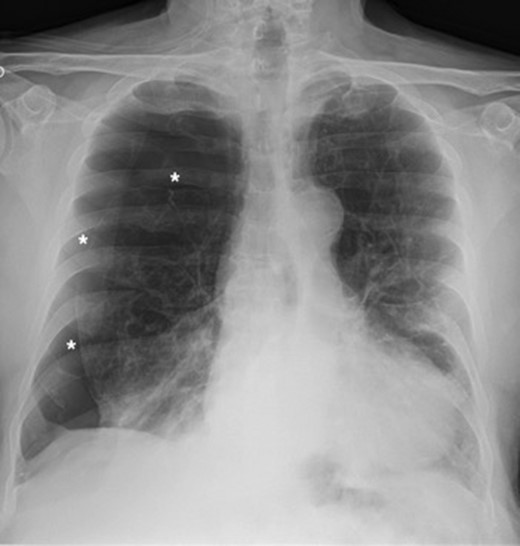

A 73-year-old male patient with a clinical history of COPD, lung emphysema and a 30-year smoking history was admitted to the ED due to a 24-h clinical picture of dyspnea immediately following a sudden bout of dry coughing. Physical examination showed a dyspneic patient, tachypnea of 25 rpm, heart rate of 85 bpm and blood Pressure of 135/75 mmHg along with central cyanosis. Chest exam showed a hyper-resonant right hemithorax along with reduced breath sounds. Initial chest X-ray revealed a large right-sided pneumothorax (Fig. 1). A right chest tube was placed in the ED. Emergency echocardiogram had no significant findings and spirometry showed suspected patterns of obstruction. Following patient stabilization, a high-resolution chest computed tomography (HRCT) was performed revealing extensive pan lobar emphysema throughout both lungs, para septal emphysema in both the anterior upper lobes and herniation of a left lung bullae through the anterior mediastinal pleura along with a right-sided pneumothorax with the chest tube in place with persistent air space (Fig. 2). The patient was taken to surgery where a right video-assisted thoracoscopic (VATS) approach showed severe lung emphysema and a contralateral herniated left lung bulla through the mediastinal pleura anterior to the pericardium (Fig. 3). Right pleurodesis was performed using Talc and a left posterior thoracoscopy showed a severe emphysematous left lung with a lingular herniated bulla to the right hemithorax through an anterior mediastinal pleural defect along with pleural adhesions (Figs 4 and 5). Thoracoscopic hernia reduction was performed along with bullectomy using 60 mm mechanical sutures (Fig. 6). Chest tubes were removed on POD 3 (right) and POD 4 (left). The patient had significant respiratory improvement and was discharged on POD 5.

Thoracoscopic view of transmediasinal herniation of pulmonary bulla to the right hemithorax (asterisk).